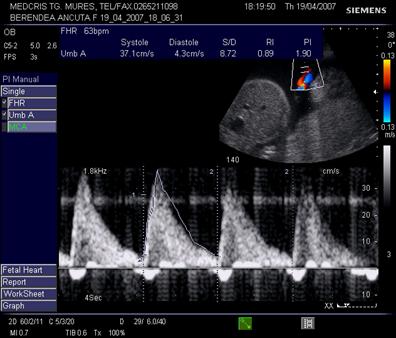

Fig. nr.243 Aparitia reverse flow in artera ombilicala , la sarcina de 28 sapt din figurile precedente, cu hidrops fetal. Se remarca bradicardia fetala si indicele mare de rezistenta in artera ombilicala